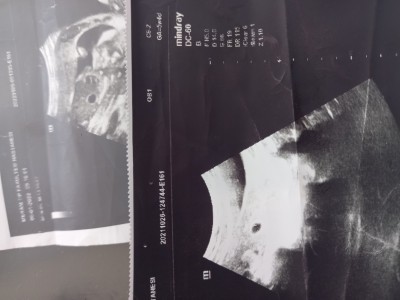

Normal mi sizce tecrübeli hanımlar Dr biraz umutsuz konuştu

Gebelik haftası 5+1

Neden umutsuz konustu kese vare yani normal 5 haftalık kese daha

Neden umutsuz konustu kese var yani normal 5 haftalık kese daha..

Evt kese var 4gun geriden geliyor dedi kasıklarımda ağrı var korkuyorum

Bak canım  kese küçük  bebek oluşması biraz zaman  var belki geç döllenme olabilir adetine üzerine de hamile kalmış olabilsin belki  adetin bittikten sonrada bekle 8 haftaya kadar kanama leke yoksa bekle her doktor  dediğine bakma bende 5 haftalık gitim kesem küçüktü Allah şükür 31 haftalık olduk bekle hata başka doktor  gir 2 hafta dayan Allah izniyle bu ramazan ayında rahim yüzünü  güldürecek  bekle güzel şeyler beklemeye  değer benim burda 5 hafta 4 günlük

Yok hayır kese var bebek yok dedi görünmedi Dr biraz şüpheli konuştu